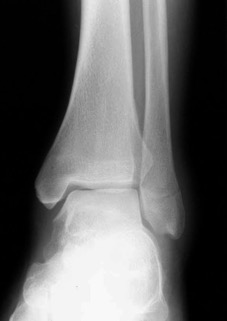

# cheville: score de Weber

Fracture de type Weber A : fracture en-dessous de la syndesmose ; l`articulation est encore mobile.

Fracture de type Weber B : fracture à hauteur de la syndesmose ; souvent le ligament est touché à cause d'un mouvement de rotation mais l`articulation peut encore être mobile.

Fracture de type Weber C : fracture au-dessus de la syndesmose ; le ligament est déchiré à cause d'un mouvement de translation latérale.